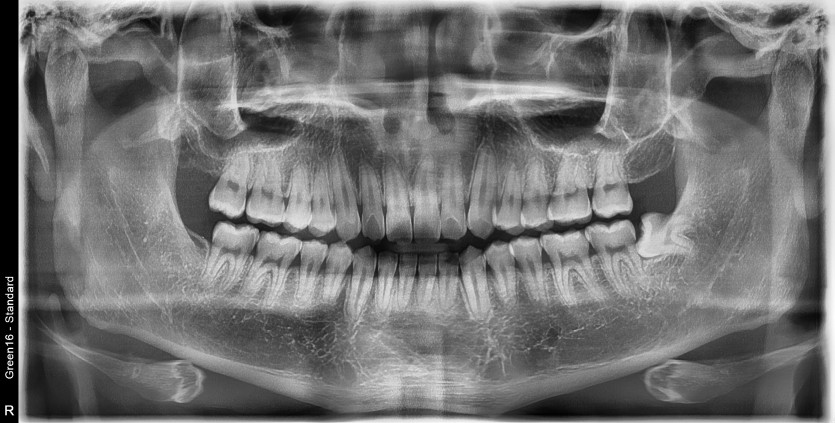

#48 사랑니 발치

구강 외과 전문의가 당일 발치했습니다.